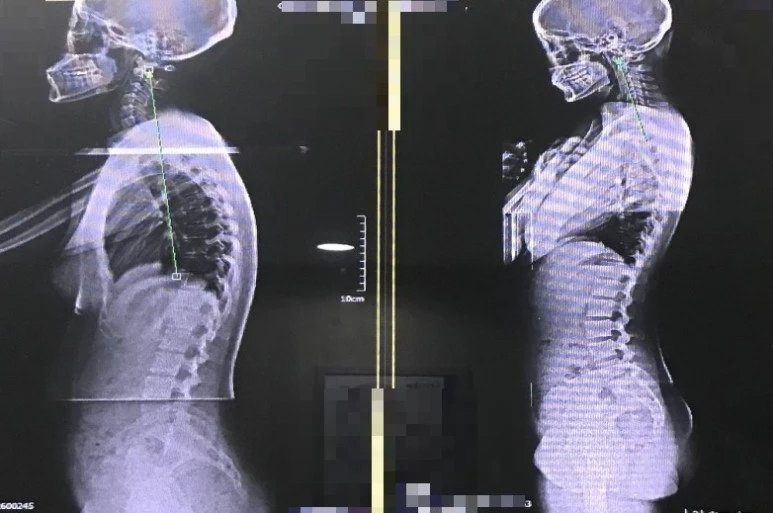

X-ray : 약 3만 원

목디스크, 경추성 두통을 확인하기 위해 엑스레이 사진을 찍었다. 나중에 확인해 보니 경추 3매, 요추 2매, 전척추 2매로 총 7매를 찍었다는 걸 알 수 있었다.

정상적인 사람은 목이 C자 형태인데, 나는 거북목까지는 아니지만 일자목이었다. 일자목이 계속 진행되면 거북목까지 갈 수 있다고 한다. 일자목으로 인해 두통이 올 수도 있지만, 현 상태의 잦아들지 않는 매우 심한 두통의 원인으로 보이진 않았다.

왼쪽이 정상, 오른쪽의 곧은 목뼈가 내 사진이다